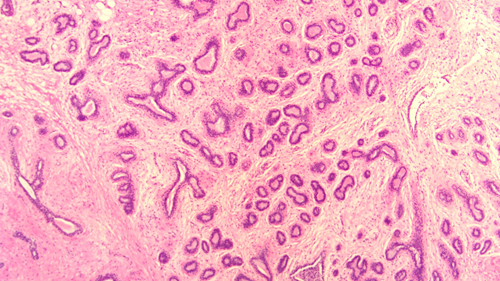

乳腺纤维腺瘤与周围正常腺体组织分界清楚,显微镜下可见其由良性的乳腺上皮和间质成分增生形成,细胞形态温和,无异型性。根据组织形态,可大致分为管内型和管周型,但分型对临床预后并无显著影响。该肿瘤经完整手术切除后,一般不会复发。

(图2:边界清晰的管内型纤维腺瘤)